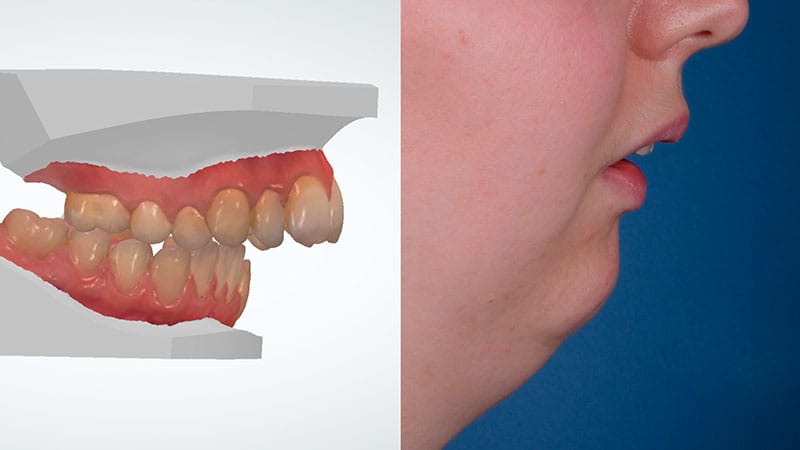

Te ofrecemos dos métodos de Ortodoncia Quirúrgica para corregir problemas severos de maloclusión y estructura facial, con un enfoque personalizado y adaptado a las posibilidades biológicas de cada persona.

Si te preocupa la forma de tu rostro o tienes una discrepancia ósea severa, este tratamiento combina ortodoncia y cirugía maxilofacial para lograr una armonía facial y funcionalidad óptima. En Clínica Friedländer, trabajamos de forma coordinada para asegurar resultados precisos y satisfactorios.

Si tu prioridad es mejorar la forma en que muerdes y no tienes una gran discrepancia ósea, este tratamiento puede ser la solución adecuada para ti. En Clínica Friedländer hemos desarrollado un protocolo avanzado que permite corregir maloclusiones severas sin necesidad de cirugía maxilofacial.